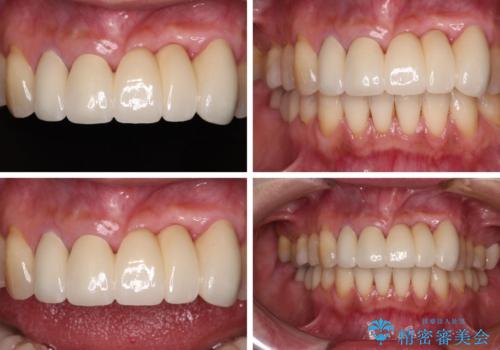

- 前歯の歯肉の腫れを気にして来院された患者様です。

前歯のみならず、奥歯の銀歯や下顎前歯のデコボコなど、色々と気になる部分を治したいとのことでした。

前歯は抜歯が必要であったので、抜歯を行い、その後歯肉移植をおこなった上でオールセラミックブリッジによる補綴治療を行うこととしました。

下顎と上顎臼歯部については矯正治療を行い、奥歯の欠損部位はオールセラミックブリッジを、その他の銀歯はセラミックインレーなどにより治療を行うこととしました。

気になっている部分を全て治療したことで、費用はかかりましたが、仕上がりには大変満足していただき、治療をおこなって良かったと仰っていただきました。